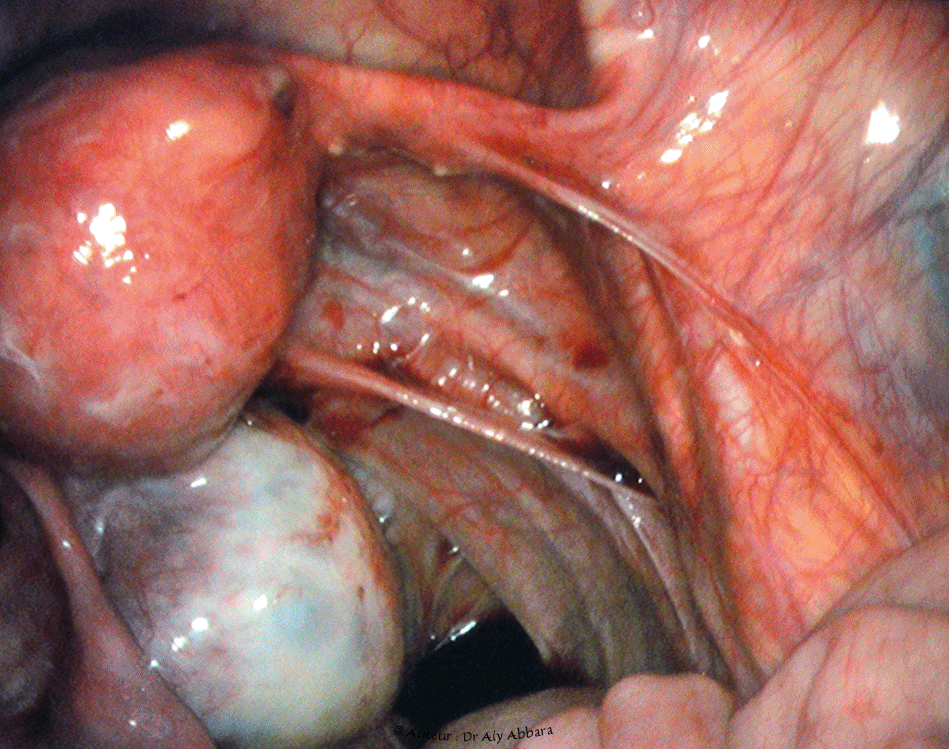

Image clinique coelioscopique montrant le reflux rétrograde, utéro-tubo-abdominal de sang menstrul (règles rétrograde)

Image clinique cœlioscopique animée, puis images échographiques par voie endovaginale (une coupe sagittale médiane sur un utérus rétroversé et une coupe longitudinale sur l'ovaire gauche) ; ces images illustrent le reflux rétrograde, tubo-abdominal de sang menstruel qui peuvent survenir au cours de certaines règles (menstruation ou menstrues rétrogrades).

Chez cette patiente, ce reflux menstruel tubo-abdominal assez important était à l'origine de règles extrêmement douloureuses (dysménorrhéique). Les douleurs pelviennes sont provoquées par l'irritation et la réaction inflammatoire du péritoine pelvien par le contact avec le sang de la menstruation qui a atteint la cavité péritonéale par voie rétrograde (cavité utérine > lumière de la trompe gauche > cavité péritonéale).

A noter que chez patiente, l'image cœlioscopique montre l'absence des annexes utérines droites (trompe et ovaire) : antécédent d'annexectomie unilatérale droite pour torsion nécrosante de ces annexes.